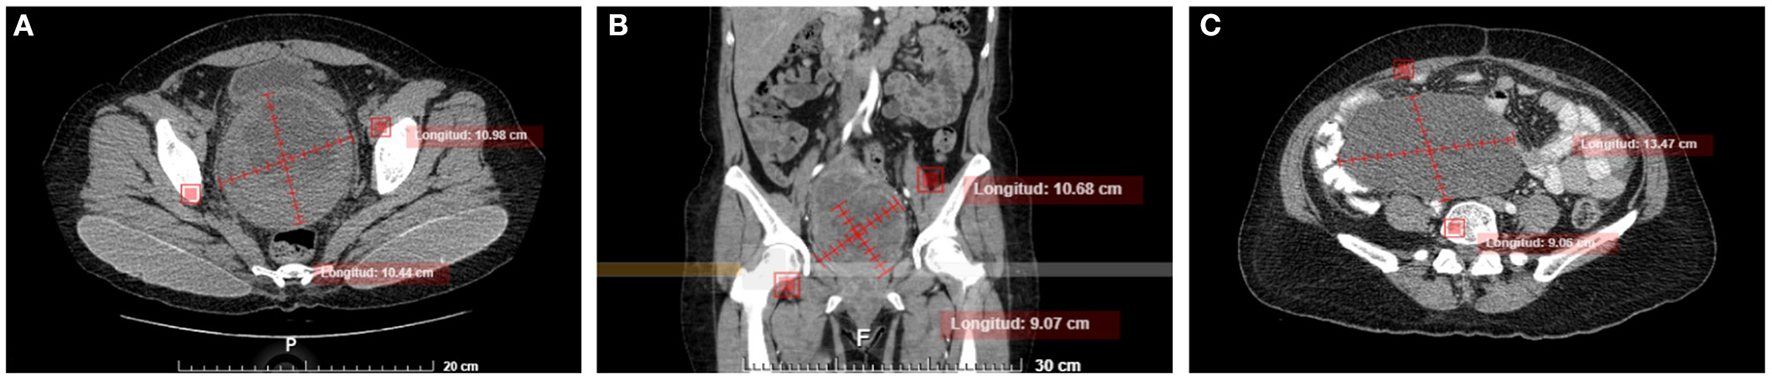

Figure 1

Abdominal axial (A) and coronal (B) non-enhanced CT images show a large well-defined rounded tumor, with a heterogeneous appearance in the cervix and demonstrating mass effect in adjacent structures and preserving interface with the bladder wall and rectum. (C) Axial non-enhanced CT, three months after surgery shows a heterogeneous abdominal tumor that compresses and displaces adjacent structures.

The patient was discharged and was kept under active surveillance by the oncology service, and without receiving adjuvant therapy. However, three months after the surgery, the patient presented intermittent abdominal pain. Abdominopelvic computed tomography was performed identifying a tumor adhered to the pelvic and abdominal cavity with dimensions of 30 × 25 cm (Figure 1C), with multiples peritoneal implants, for which she was operated on again. The patient underwent optimal debulking plus packaging, presented bleeding of 5,000 ml, 4 globular units and expander fluids were administered. We received in the Pathology department, a multifragmented tumor with a soft necrohemorrhagic appearance, and in the histological study with the characteristics already mentioned above. During her hospitalization, she developed pulmonary embolism. A pulmonary embolism computed tomography was performed, where a thrombus was evidenced in the right pulmonary artery, which led to a pulmonary infarction of the right lower lobe. Acenocoumarin was administered, despite this, she developed right lower extremity thrombosis. It was assessed by the Departments of Clinical Oncology and Radiotherapy, concluding that it was out of clinical treatment based on the added underlying pathologies. He is currently in palliative treatment, with acenocoumarin and morphine for pain management.